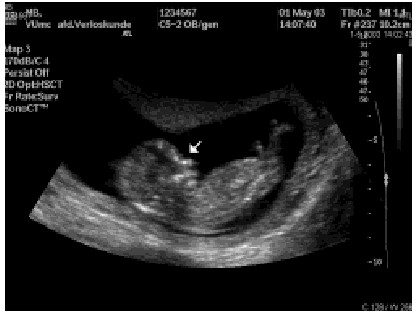

Het Down-syndroom is een ernstige chromosomale afwijking (trisomie 21) die leidt tot ontwikkelingsachterstand en morfologische afwijkingen. In de meerderheid van de gevallen is de trisomie 21 nieuw ontstaan door een verdelingsfout van de chromosomen nummer 21 tijdens de meiose. De…